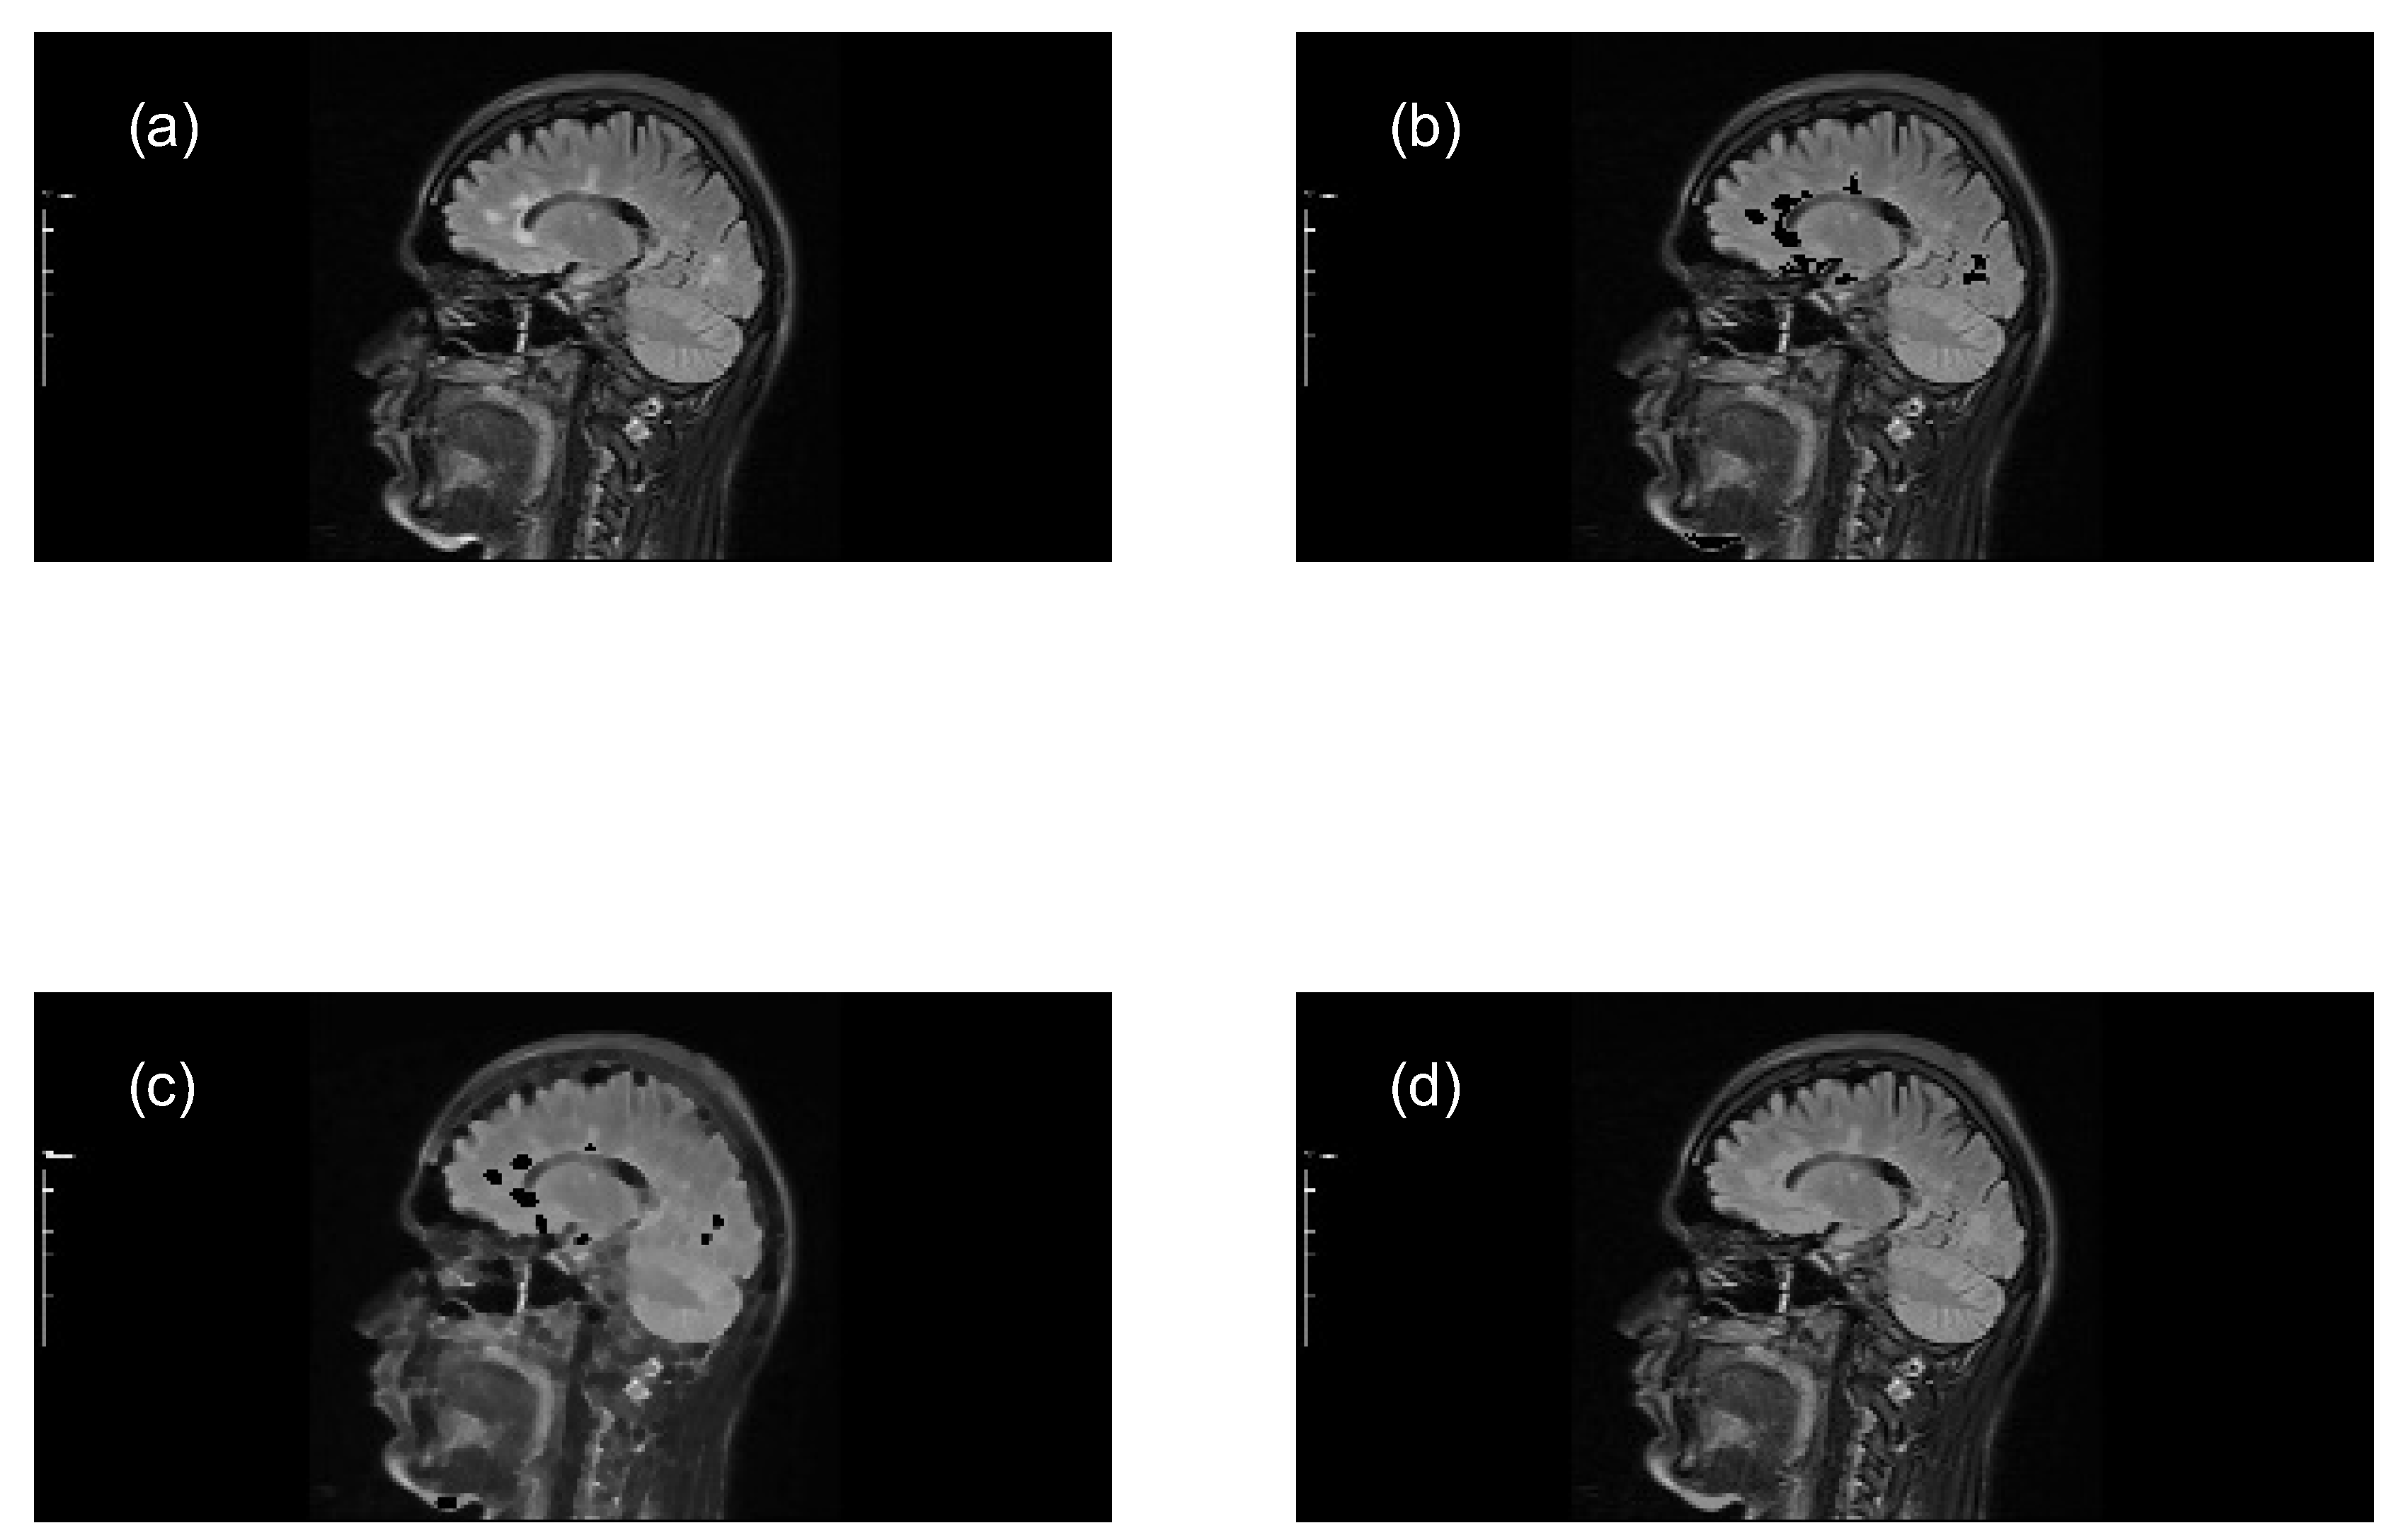

Perform closing morphological transformations on brain images of MS patients (axial and sagittal MRI) to determine the size of the MS lesions, applying the following steps:

- Subtract the lesion areas from the mask image (original image) to acquire a brain image without lesions (with holes).

- Perform a morphological closing transformation on the resulting image (previous step) using a disk-shaped SE with radius r to create a marker image. This operation consists of a dilation followed by erosion using the same SE.

- Perform a closing by reconstruction transformation on the marker image (Equation 6), using the mask image to fill the holes and create a reference image (without lesions), for making comparisons with the mask image (with lesions).

- Compute the granulometry of objects of the mask image and the reference image for different values of radius () of the SE.

- Determine the size of MS lesions by computing the differences in granulometry measurements of the mask image and the reference image to support the decision of specialists in estimating the disease progress.